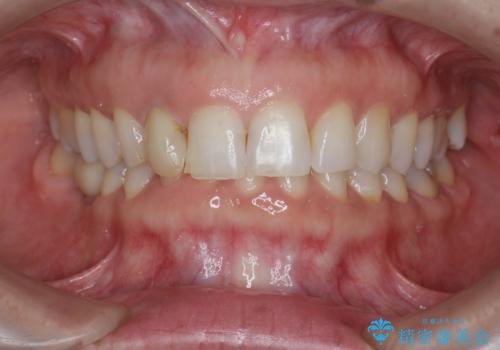

前歯の違和感 失活歯の根管治療とセラミック治療

- 前歯の付近、歯ぐきを押すと違和感を感じその改善を求めて来院されました。

X線検査の結果、失活(感染根管)であることが判明したので、感染根管治療後セラミック補綴を計画します。

- 16万円(仮歯・ファイバーコア・ジルコニアクラウンスペシャル)費用は治療当時の料金となります